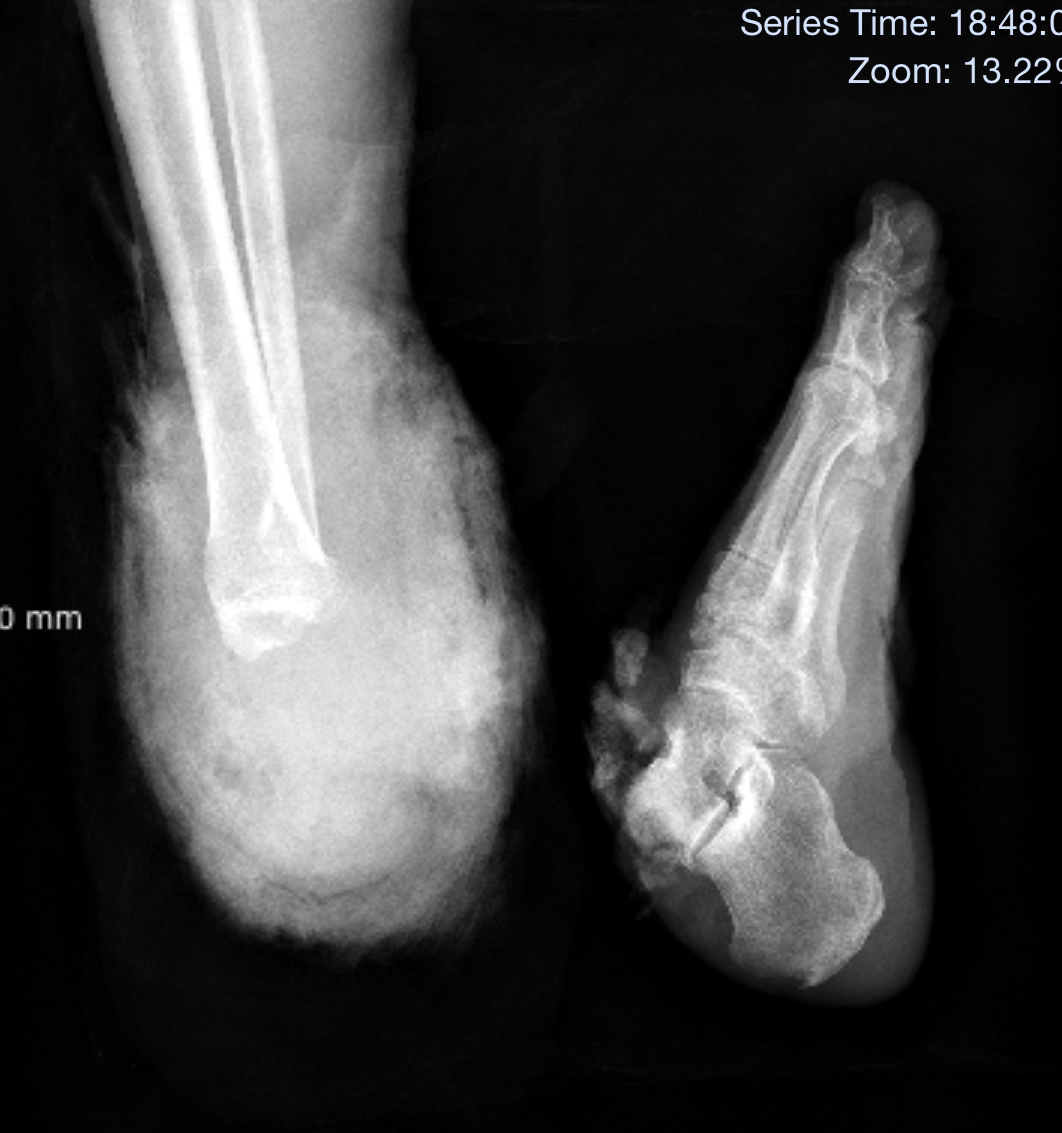

日常生产作业,务必做足防护措施,小心谨慎,以免发生意外。近日,常州金坛一名工人张先生在工作时发生意外,右足在脚踝部位完全离断,骨骼、肌肉、神经、血管断裂外露,断端大量出血,被紧急送到了南医大三附院(常州二院)阳湖院区急诊。

经过大量输血等积极抢救后,患者生命体征相对平稳,手术室里的再植专家们在无影灯下、显微镜前已做好了“鏖战”的准备。术中医生们分别对患者断足的近端伤口和远端离断部分进行处理:清创、去掉污染组织,修整骨折断端,标记重要血管、肌腱位置,克氏针外架固定……一切都熟练紧凑、有条不紊。